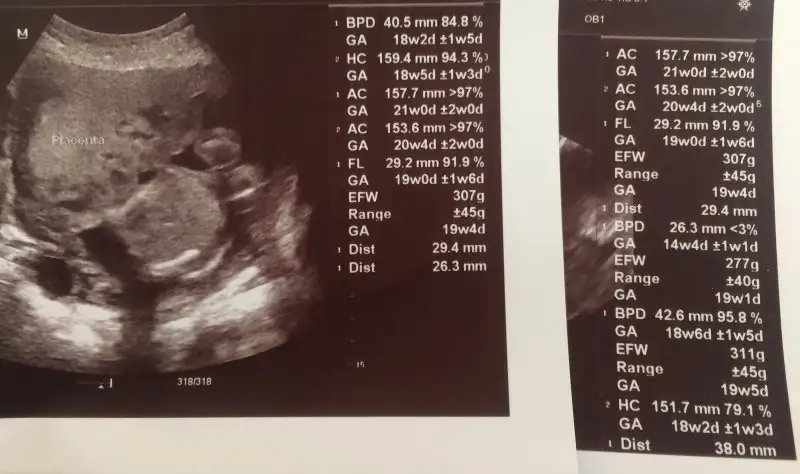

Canım doktor sanırım kafa, bacak ve karın ölçümleri de yapmış. FL,AC ve AG onlardı yanılmıyorsam. İlk çocuğumdaki devlet doktorum hep böyle bakardı rapora da yazardı hatta. Baya ayrıntılı bakmış yani doktorun maşallah... Bu arada bebek büyüdükçe ölçümler tam yapılamıyor. Kafa önde bacak arkada ya da tam tersi olabilir. Arada çok fazla fark olmadığı sürece ve bu fark artarak devam etmediği sürece problem yok bildiğim kadarıyla.Eveeettt. Annelerin merakı bitmez. Bu terimler ne? Niye bazısı hafta olarak büyük, bazısı çok daha büyük?

İnternetten baktım şimdi, öyleymiş. Tabi araştırıcam derken şaşı olucam yakında, gözlerim ağrıdı yavvv. AC ye taktım 3haftadan fazla önde. Karın çevresi oluyormuş. Babası da anası da kalın belli. Ne bekliyorsam :)Canım doktor sanırım kafa, bacak ve karın ölçümleri de yapmış. FL,AC ve AG onlardı yanılmıyorsam. İlk çocuğumdaki devlet doktorum hep böyle bakardı rapora da yazardı hatta. Baya ayrıntılı bakmış yani doktorun maşallah... Bu arada bebek büyüdükçe ölçümler tam yapılamıyor. Kafa önde bacak arkada ya da tam tersi olabilir. Arada çok fazla fark olmadığı sürece ve bu fark artarak devam etmediği sürece problem yok bildiğim kadarıyla.